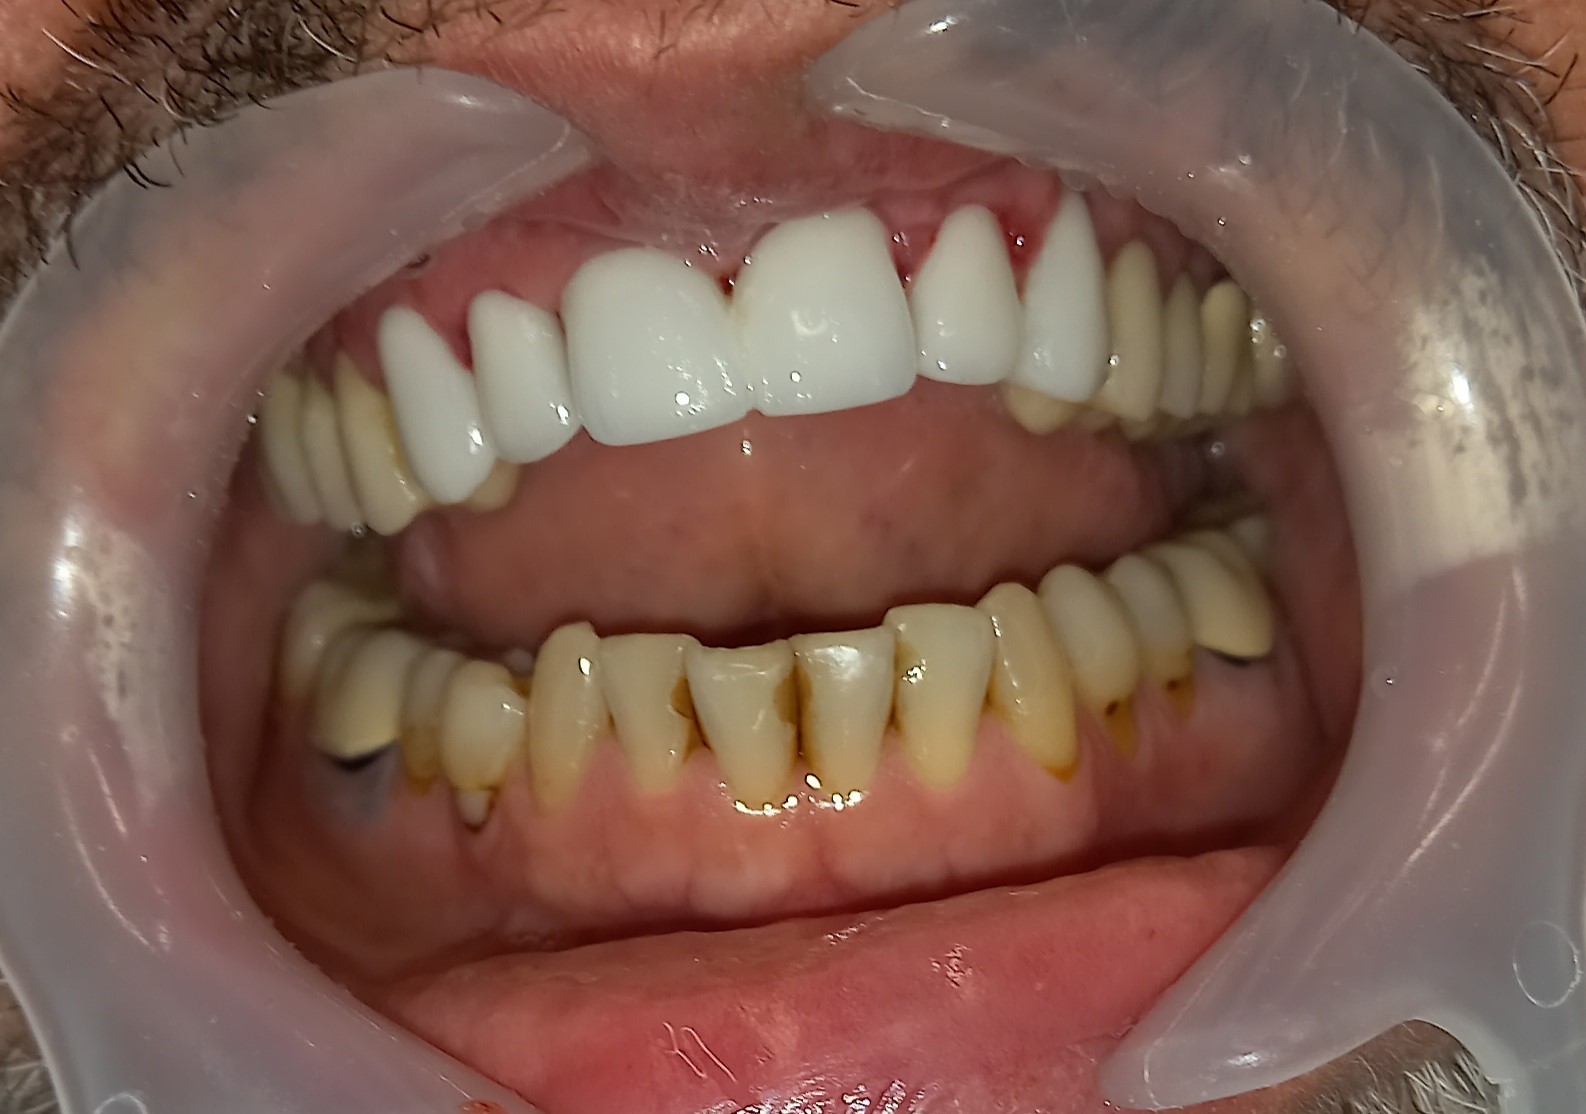

Ο ασθενής δεν είναι ευχαριστημένος με την αισθητική των 6 άνω πρόσθιων δοντιών. Επιπρόσθετα αυτά τα δόντια είχαν παλιές μεγάλες ανασυστάσεις, οι οποίες είχαν επανατερηδονιστεί. Για όλους τους ανωτέρους λόγους αποφασίστηκε, μετά από την απαραίτητη συζήτηση με τον ασθενή η αποκατάσταση των δοντιών με ολοκεραμικές θήκες. Τα δόντια τροχίστηκαν, αντικαταστάθηκαν οι παλιές εμφράξεις των δοντιών και στη συνέχεια λήφθηκαν αποτυπώματα, τα οποία στάλθηκαν στον οδοντοτεχνίτη. Σε όλη τη διάρκεια, που ο οδοντοτεχνίτης κατασκεύαζε τις νέες προσθετικές αποκαταστάσεις ο ασθενής φορούσε προσωρινές θήκες, οι οποίες είχαν ικανοποιητική αισθητική εμφάνιση.

Είναι σημαντικό να τονιστεί οτι ο ασθενής επιθυμούσε οι θήκες των 6 άνω πρόσθιων δοντιών να είναι αισθητά λευκές, παρόλο που διέφεραν χρωματικά από τα υπόλοιπα δόντια.

Ο ασθενής είναι ευχαριστημένος τόσο με την αισθητική όσο και με τη λειτουργία των νέων προσθετικών αποκαταστάσεων.

Αρχική κλινική εικόνα των 6 άνω πρόσθιων δοντιών

Προσωρινή αποκατάσταση των 6 άνω πρόσθιων δοντιών

Τελική κλινική εικόνα των 6 άνω πρόσθιων δοντιών